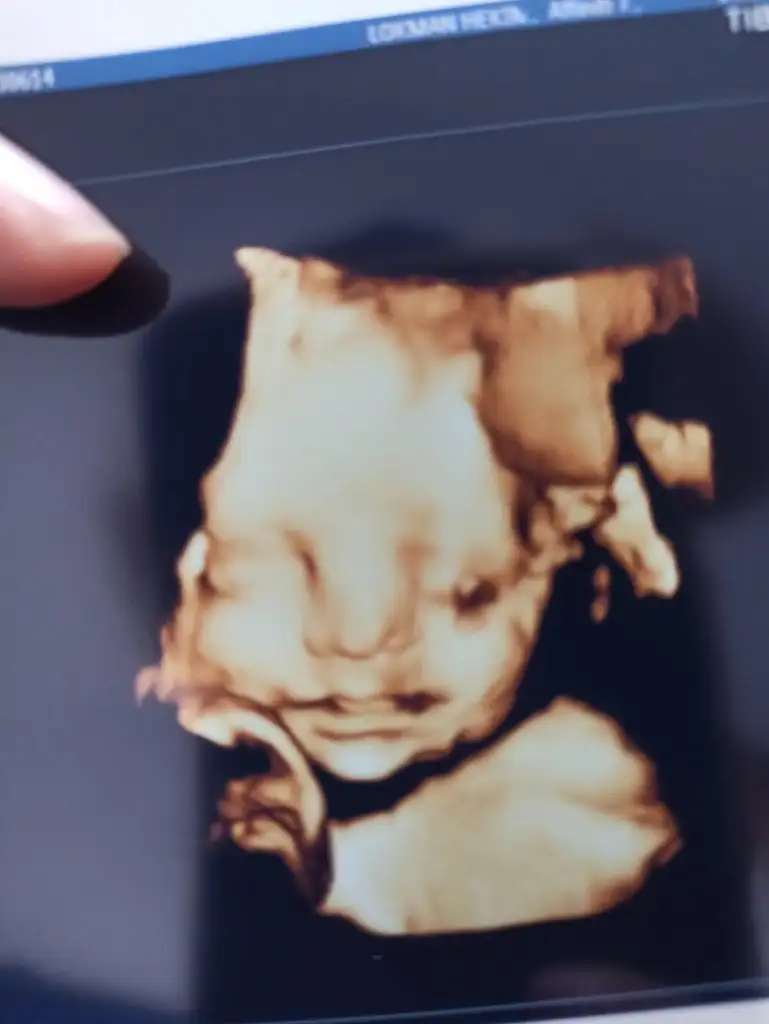

Kadın doğum doktorum iki haftada bir kontrol olmamı suyun fazlalaşıp bebeğin irileşip irileşmediğini takip etmemiz lazım dedi bugünki muayenemde bebeğimin günüyle gayet uyumlu olduğunu ve önden gitmediği için bunun sevindirici bir durum olduğunu söyledi. Şekerine dikkat et şeker yükselirse otomatik men suyuda fazlalaşır ve bu bebekte irileşmeye sebebiyet verir biz bunu asla istemeyiz dedi. Suyun 200 altı olması lazım senin 170 aslında yine fazla ama en azından bu seviyede bile ilerlesek bize bir sorun çıkarmaz dedi. Kilomu tarttı 8 kilo almışsın buda gayet uygun dedi. Zaten kızlar diyet yaptığımdan beri kilo almıyorum zaten yediklerimde sınırlı. boy 35cm 1100 gram bir minnakım var resmimizi de koydum teyzeleri bakarsınız dil çıkardı bize doktor da yakaladı o anda güldük baya ağzını açıp kapatıyordu miniğim bugünlük bizden bu kadar bilgi teyzelerimiz kızımla sizi çok çok öpüyoruz